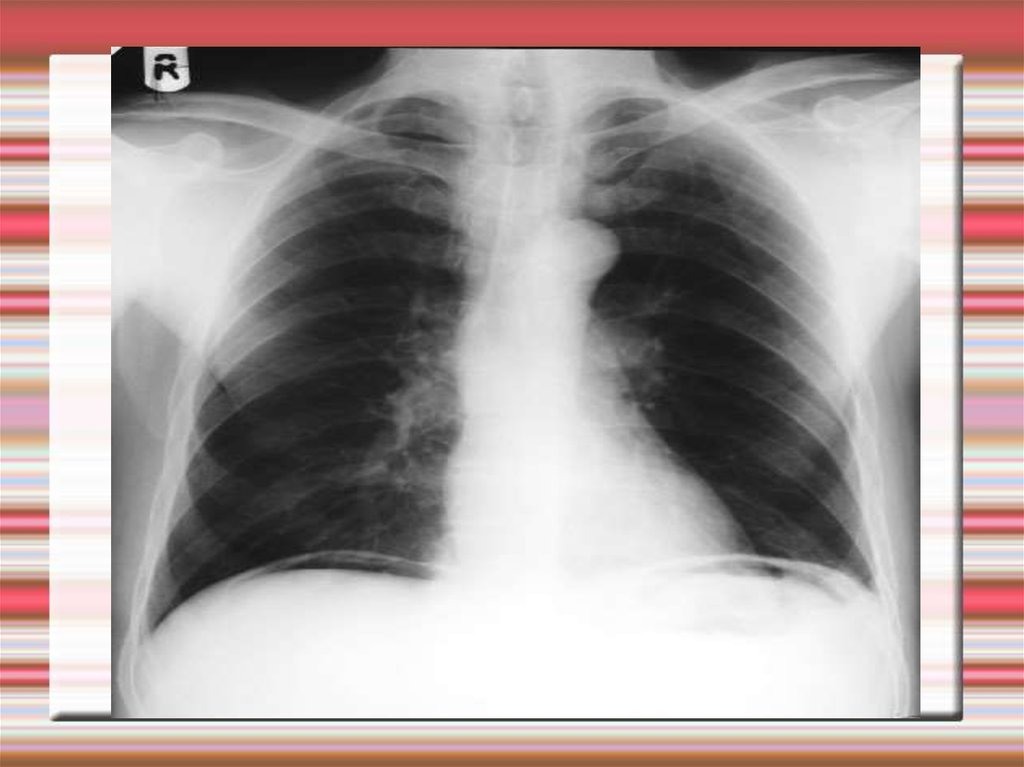

Перфорация дивертикула

При перфорации в жировой подвесок или брыжейку развивается

абсцесс.

Каловый перитонит развивается при

перфорации в свободную брюшную

полость.

Диагностируется на основании

клинических и инструментальных

признаков, обнаружения свободного

газа в брюшной полости